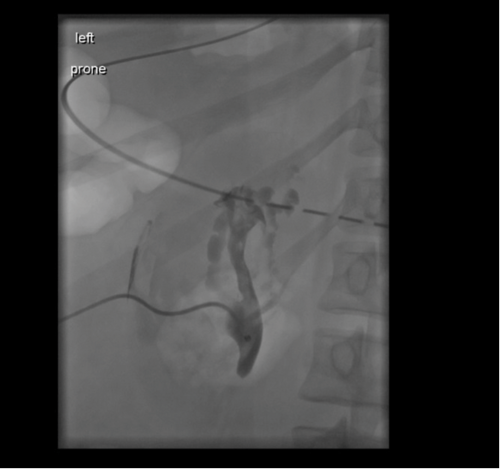

Figure 1: Nephrostogram demonstrating ligated PUJ.

A 24-year-old patient was transferred from a referring hospital following ureteric avulsion at the time of ureteroscopy. Ureteric injury was recognised at the time of surgery and a laparotomy performed. The ureter was found to be avulsed at both the PUJ and vesicoureteric junction (VUJ). The PUJ was ligated (Figure 1) and the patient transferred for definitive management. On arrival a nephrostomy was inserted for renal drainage until definitive management was decided. The following management options were considered and discussed with the patient:

A magnetic resonance angiogram (MRA) scan demonstrated paired renal arteries with single renal veins. A dimercaptosuccinic acid (DMSA) was performed to document the split function, which revealed 49% function on the affected side. The eGFR based on serum creatinine was >90mL/min/1.73m2.